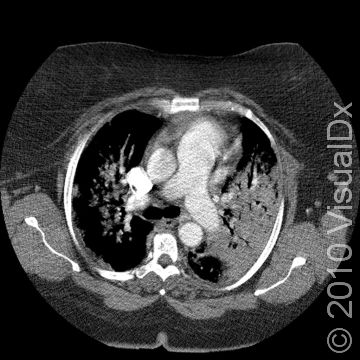

In order to diagnose legionellosis, your doctor will need to perform specific tests on your sputum (the material that you cough up) and your urine to confirm the presence of the bacterium. The doctor may order a chest X-ray to confirm the diagnosis of pneumonia. There is no definitive blood test for legionellosis. Common antibiotics are used to treat legionellosis.